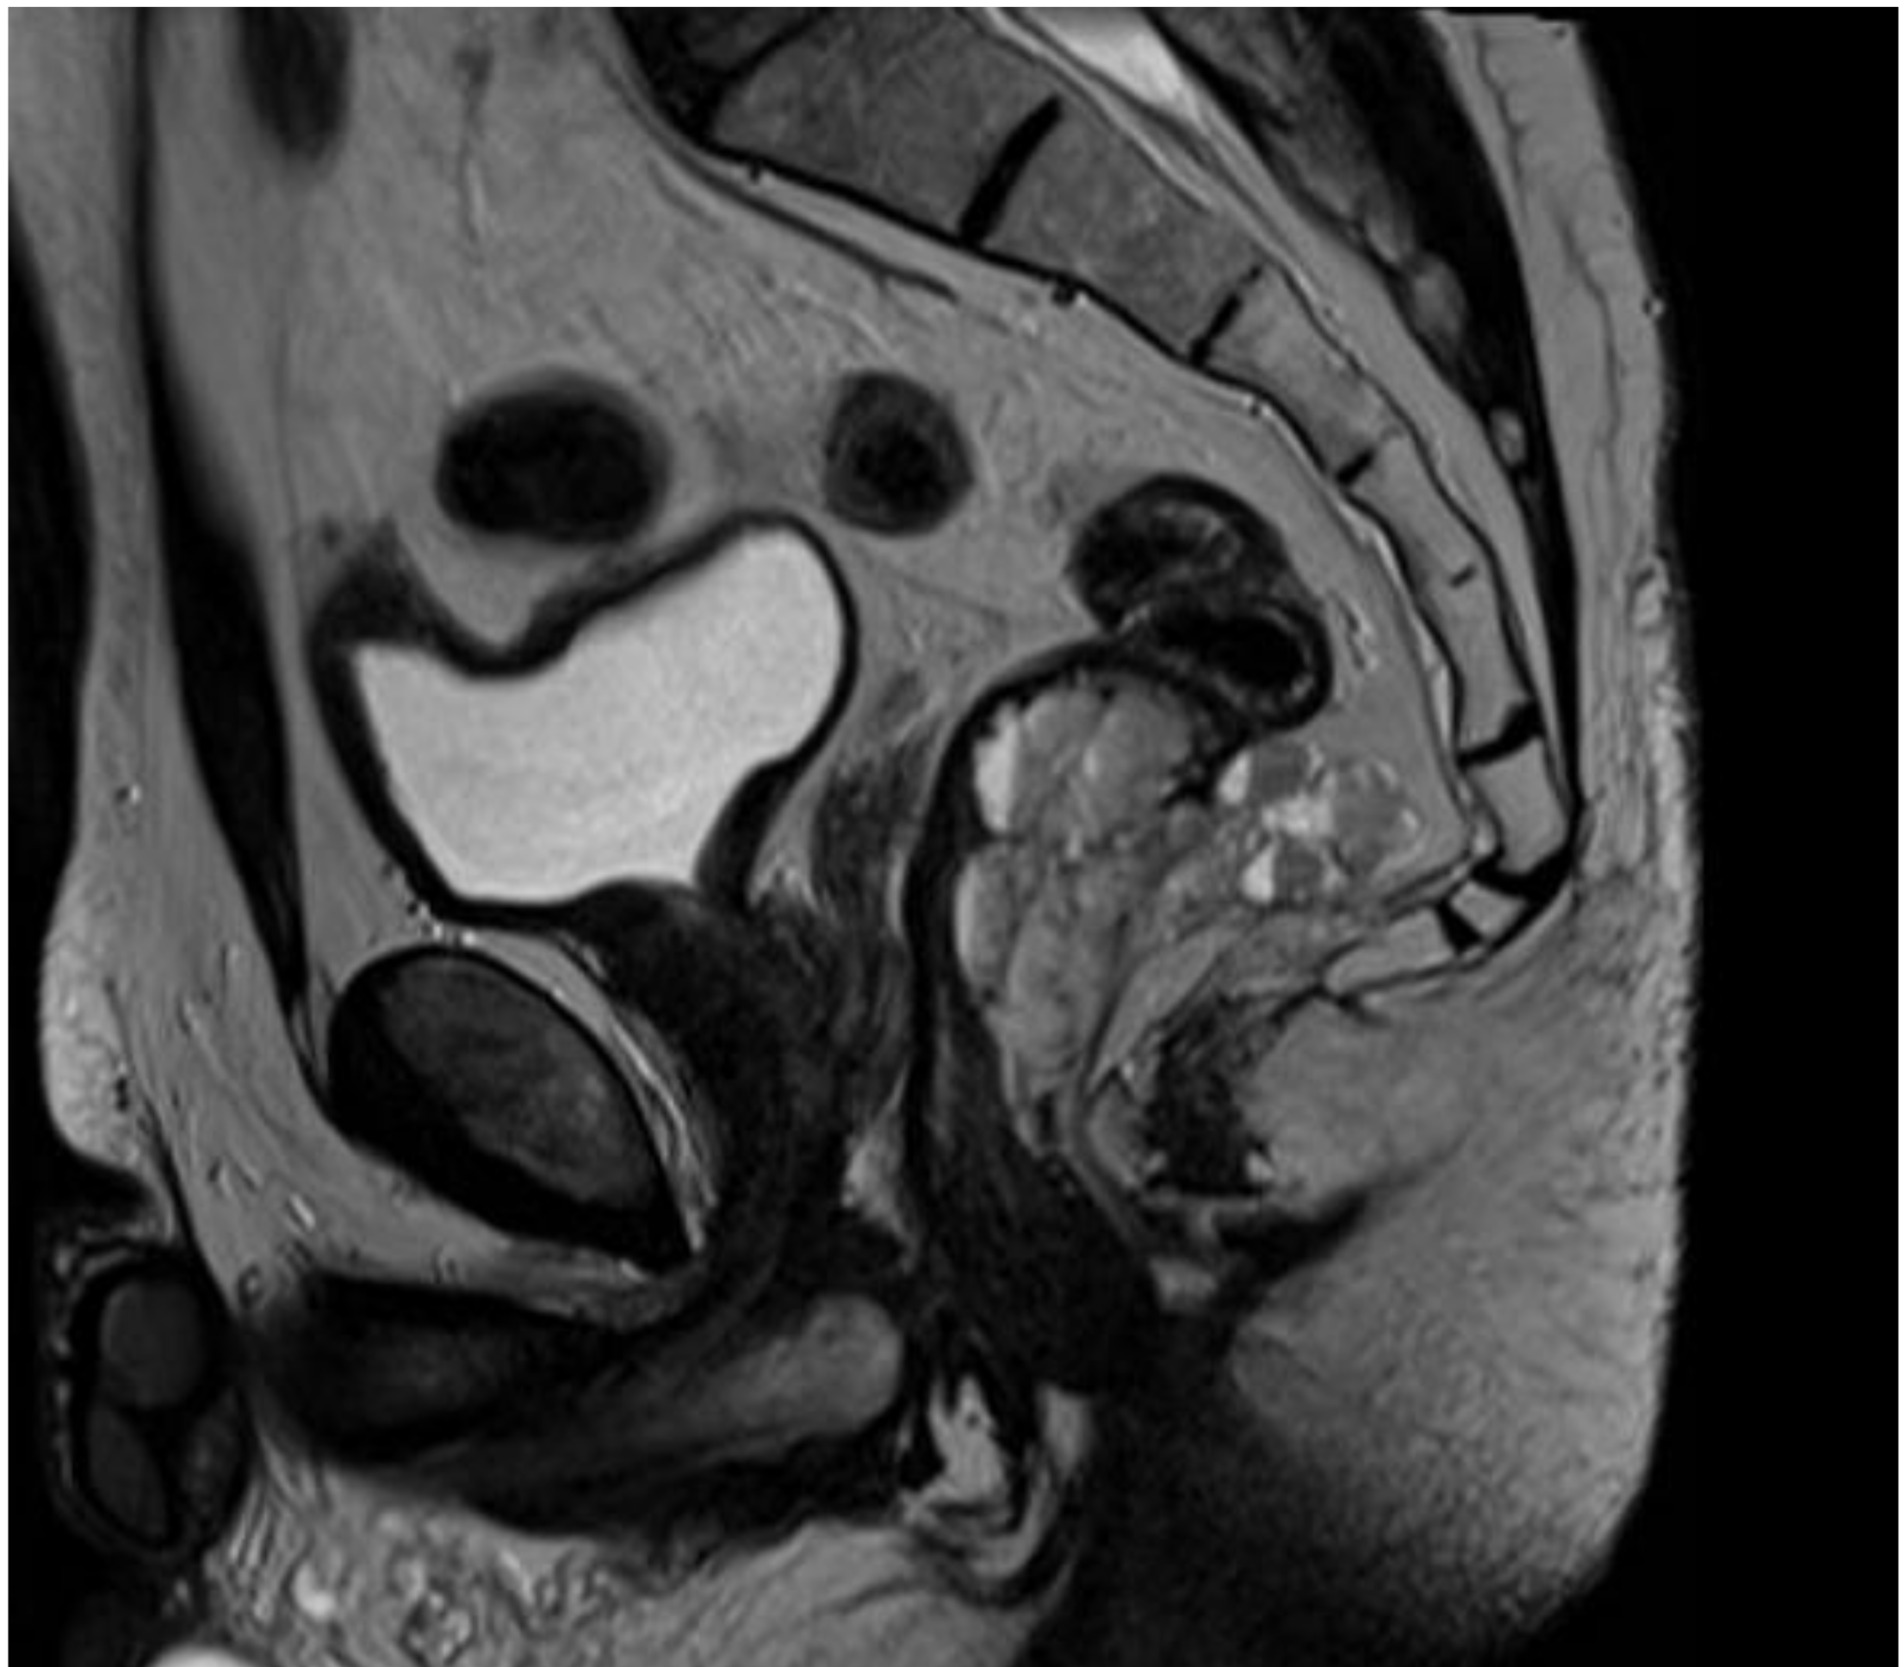

We report the case of a 52-year-old male patient in whom a vegetative lesion of the distal rectum was incidentally identified during urological evaluation for bladder carcinoma. The patient’s medical history was notable for episodes of hematochezia, which had not previously undergone proctological assessment. Endoscopic investigations were conducted (Figure 1); however, biopsy specimens yielded non-diagnostic results. Computed tomography (CT) imaging demonstrated apparent obliteration of the distal rectal lumen by a parietal mass measuring approximately 4 cm. To further characterize the lesion, contrast-enhanced MRI was performed, confirming the presence of an expansive mass in the distal rectum (Figure 2).

Inhomogeneous signal hyperintensity in T2-weighted sequences with a fluid/fluid level appearance, isointensity signal in T1-weighted sequences, no signal reduction in T1-weighted sequences in opposition of phase in agreement with the absence of a lipid component, no signs of signal restriction in diffusion (ADC 1.6), thin peripheral contrast enhancement, and thin septa in the structure were all features of the MRI. The lesion on the right posterolateral side appeared to affect the muscular coat, extending to the serosa raising suspicion for a teratomatous-type lesion. Following multidisciplinary consultation, surgical excision was planned. A transanal local excision was performed under general anesthesia (Figure 3). The patient’s postoperative course was uneventful, and he was discharged on the first postoperative day. Histopathological analysis revealed an edematous, ulcerated, and chronically inflamed segment of the large intestinal wall, containing lymphatic and intraparietal blood vessel ectasias consistent with hemolymphangioma. No postoperative complications were observed. The patient underwent regular follow-up evaluations, including proctological examinations, CT scans, and MRI studies (Figure 4) every six months for the initial two years, followed by annual assessments. At four years postoperatively, there is no evidence of disease recurrence.